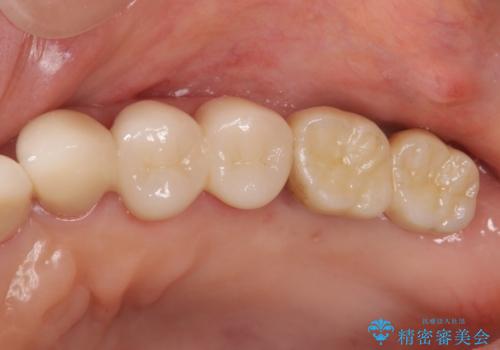

- 夜間のくいしばり、はぎしりが激しく全体的な歯周病が進行し、治療を希望され来院されました。

歯周ポケットの徹底的な除去を行なったのち、歯の揺れを抑え、過大な力がかからぬよう連結クラウン(歯周補綴)を行い強大な力に対抗します。

- 55万円(仮歯×3・ファイバーコア×3・歯周外科)費用は治療当時の料金となります